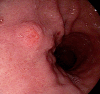

Gastric polyps (GPs) are increasingly common. On upper endoscopy, they should be examined with white light and occasionally chromoendoscopy, and their morphology classified according to the Paris classification. Most GPs have a typical endoscopic appearance and can be associated with diseases like Helicobacter pylori infection. Histological examination is necessary for an accurate diagnosis. While most polyps are non-neoplastic and do not require treatment, some carry a risk of malignancy or are already malignant. Therefore, understanding the diagnosis, classification, and management of GPs is crucial for patient prognostication. Our new classification categorizes GPs into "good", "bad", and "ugly" based on their likelihood of becoming malignant. We aim to provide descriptions of the endoscopic appearance, pathology, treatment, and follow-up for different GPs, as well as clinical management flowcharts.